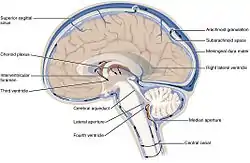

In neuroanatomy, the ventricular system is a set of four interconnected cavities known as cerebral ventricles in the brain.[1][2] Within each ventricle is a region of choroid plexus which produces the circulating cerebrospinal fluid (CSF). The ventricular system is continuous with the central canal of the spinal cord from the fourth ventricle,[3] allowing for the flow of CSF to circulate.[3][4]

There are several foramina, openings acting as channels, that connect the ventricles. The interventricular foramina (also called the foramina of Monro) connect the lateral ventricles to the third ventricle through which the cerebrospinal fluid can flow.

The four cavities of the human brain are called ventricles.[6] The two largest are the lateral ventricles in the cerebrum, the third ventricle is in the diencephalon of the forebrain between the right and left thalamus, and the fourth ventricle is located at the back of the pons and upper half of the medulla oblongata of the hindbrain. The ventricles are concerned with the production and circulation of cerebrospinal fluid.[7]

The ventricles are filled with cerebrospinal fluid (CSF) which bathes and cushions the brain and spinal cord within their bony confines. CSF is produced by modified ependymal cells of the choroid plexus found in all components of the ventricular system except for the cerebral aqueduct and the posterior and anterior horns of the lateral ventricles. CSF flows from the lateral ventricles via the interventricular foramina into the third ventricle, and then the fourth ventricle via the cerebral aqueduct in the midbrain. From the fourth ventricle it can pass into the central canal of the spinal cord or into the subarachnoid cisterns via three small foramina: the central median aperture and the two lateral apertures. According to the traditional understanding of cerebrospinal fluid (CSF) physiology, the majority of CSF is produced by the choroid plexus, circulates through the ventricles, the cisterns, and the subarachnoid space to be absorbed into the blood by the arachnoid villi.